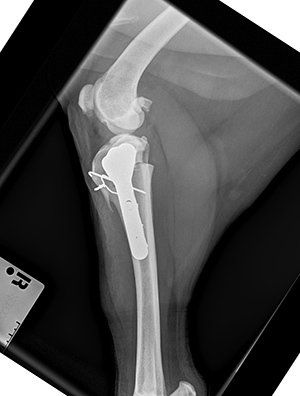

Whether it be a serious fracture, a luxating patella, a cruciate rupture, or serious joint damage, then this service can help your pet , or your patient.

Working alongside the vets and nurses who know your pet so well, I can add my expertise and experience to their on going care.